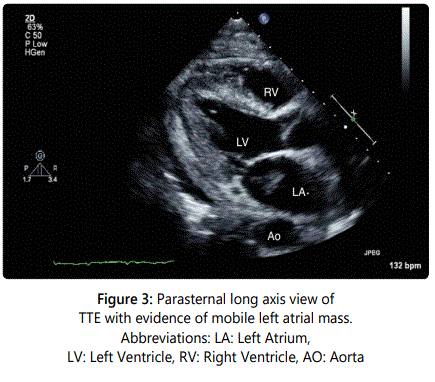

A 54-year-old gentleman with recently diagnosed Stage IIIB squamous cell carcinoma of the lung with metastases to the lymph nodes had a transthoracic echocardiograph (TTE) performed for evaluation of progressive dyspnea on exertion. A large pericardial effusion causing tamponade physiology was noted on TTE and the Computerized Tomography (CT) image of the thorax (Figures 1 and 2). Following a pericardi ocentesis, a repeat TTE was performed which showed the presence of a left atrial mass (Figure 3). The mass was initially reported as a 1.3x0.5 cm pedunculated mobile left atrial mass arising from the left atrial appendage prolapsing in the mitral orifice in diastole before further assessment with a transesophageal echocardiogram (TEE) was performed. The TEE demonstrateddirect invasion of the mass from the left upper pulmonary vein into the left atrial appendage with minimal residual flow of that pulmonary vein and complete opacification of the left atrial appendage as well as invasion of the superior vena cava (Figure 4). The mobile mass in the left atrium was a strand of tumor that extended from the edge of the left atrial appendage (Figures 5 and 6).